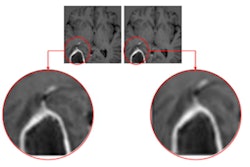

IB Clinic includes the company's IB Neuro module, which creates images of cerebral blood volume from MRI data, Imaging Biometrics said.